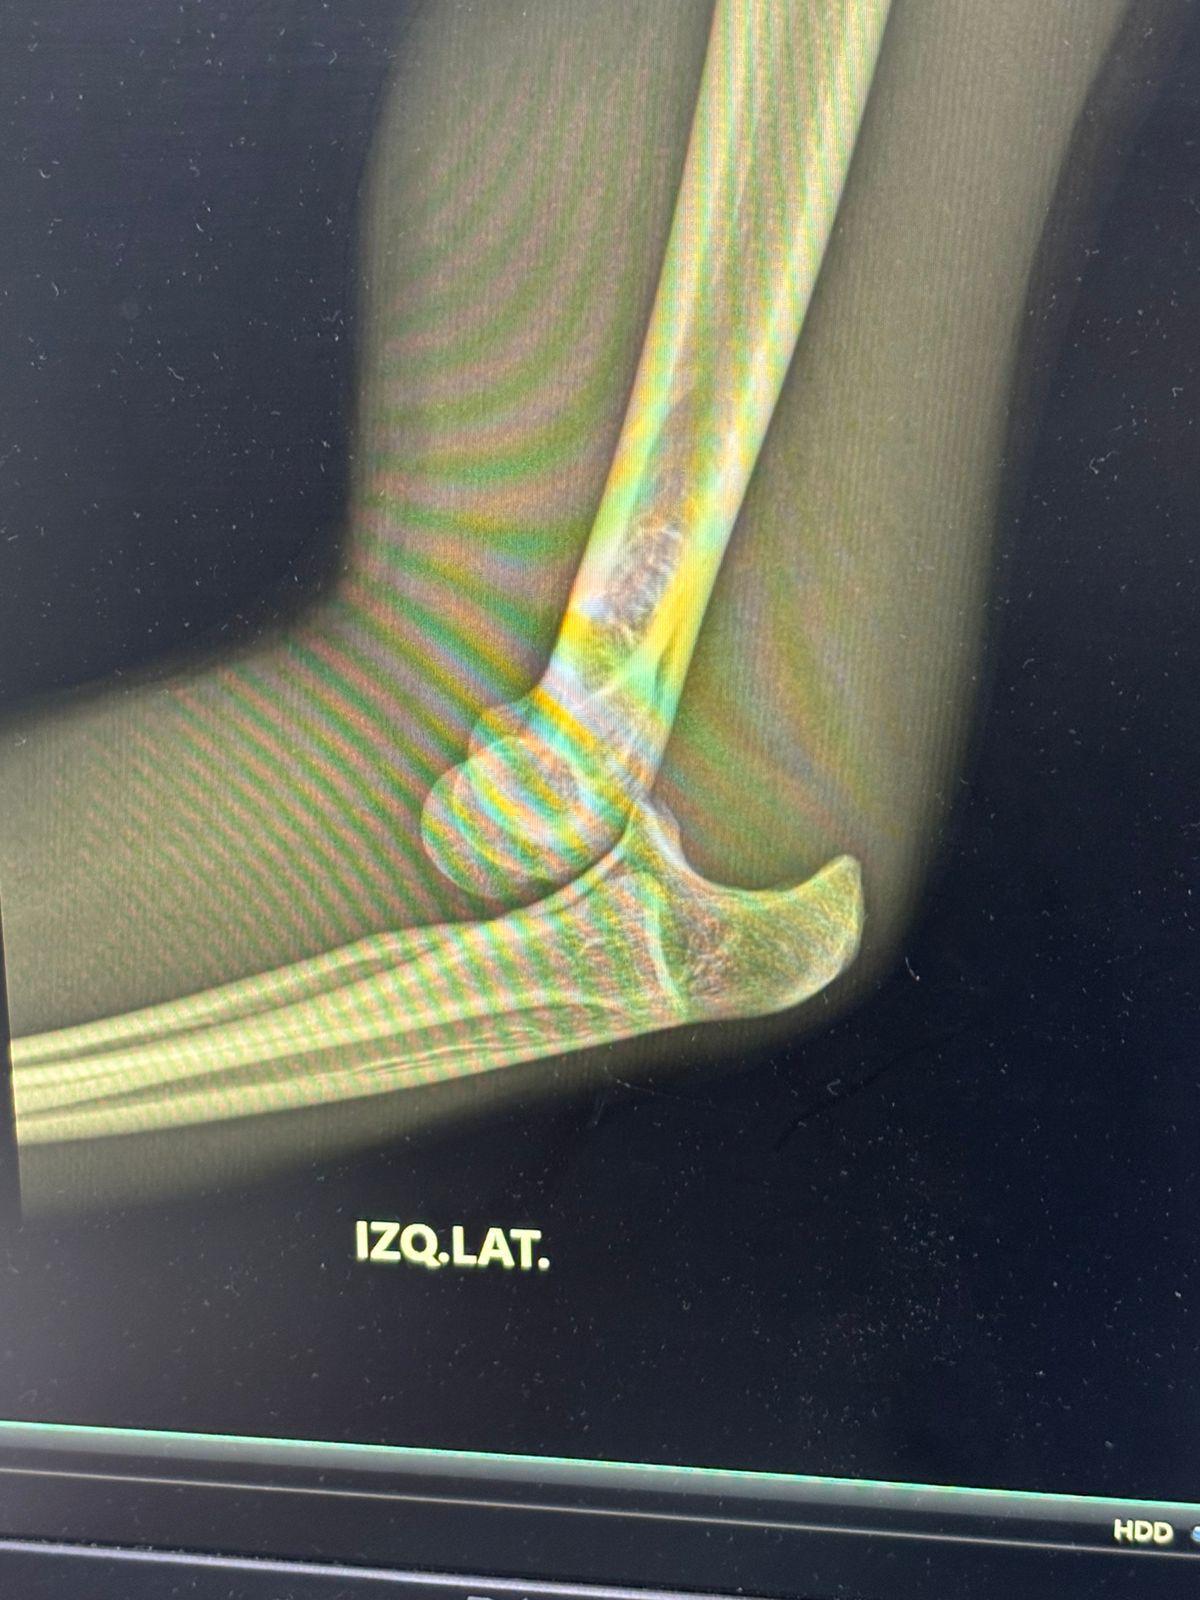

La empresa EMSA informa a la afición que el matador Sergio Garza ha sufrido un percance durante sus actividades de preparación, resultando con una luxación posterior, contusión del nervio cubital y lesión de los ligamentos de la cápsula articular del codo, lesiones que le impedirán actuar en la corrida del próximo domingo 9 de noviembre, en la Monumental “Lorenzo Garza”.